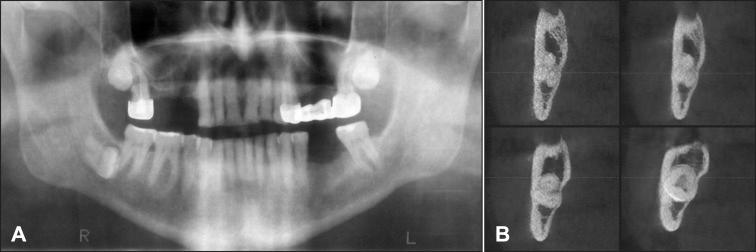

The purpose of present article was to review impacted mandibular third molar aetiology, clinical anatomy, radiologic examination, surgical treatment and possible complications, as well as to create new mandibular third molar impaction and extraction difficulty degree classification based on anatomical and radiologic findings and literature review results.

In total 75 literature sources were obtained and reviewed. Impacted mandibular third molar aetiology, clinical anatomy, radiographic examination, surgical extraction of and possible complications, classifications and risk factors were discussed. New mandibular third molar impaction and extraction difficulty degree classification based on anatomical and radiologic findings and literature review results was proposed.

The classification proposed here based on anatomical and radiological impacted mandibular third molar features is promising to be a helpful tool for impacted tooth assessment as well as for planning for surgical operation. Further clinical studies should be conducted for new classification validation and reliability evaluation.